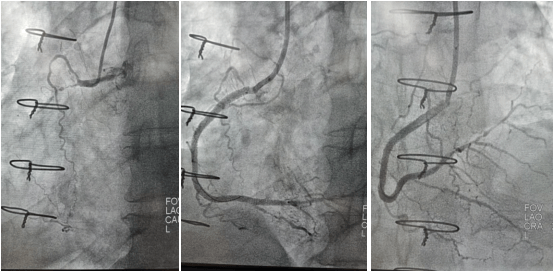

2022年9月16日行冠脉造影术,造影结果示:左主干末端99%狭窄,LAD近段100%闭塞,LCX开口及近段95%狭窄,乳内动脉-左前降支血管通畅,RCA近段100%闭塞,大隐静脉桥血管未见,考虑闭塞。

心血管病院吴栋梁院长、CCU李新国副主任、心血管内科二病区赵娟副主任、王端乐主治医师、宋睿主治医师介入团队造影后认真研究患者的病情和影像资料,决定开通闭塞长达11年的右冠状动脉,精确选择器械,选择同轴性及支撑力均好的指引导管,术中选用微导管辅助,软、硬导丝结合等技术,聚精会神、挥汗如雨,终于历经3小时的努力,成功前向开通右冠状动脉,精准选择由远及近“铺设”通过性较好、长度合适的支架 。

(术前术后对比)